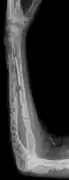

The diagnostic examination of a person with suspected multiple myeloma typically includes a skeletal survey. This is a series of X-rays of the skull, axial skeleton, and proximal long bones. Myeloma activity sometimes appears as "lytic lesions" (with local disappearance of normal bone due to resorption). And on the skull X-ray as "punched-out lesions" (pepper-pot skull). Lesions may also be sclerotic, which is seen as radiodense.[47] Overall, the radiodensity of myeloma is between −30 and 120 Hounsfield units (HU).[48] Magnetic resonance imaging is more sensitive than simple X-rays in the detection of lytic lesions, and may supersede a skeletal survey, especially when vertebral disease is suspected. Occasionally, a CT scan is performed to measure the size of soft-tissue plasmacytomas. Bone scans are typically not of any additional value in the workup of people with myeloma (no new bone formation; lytic lesions not well visualized on bone scan).

X-ray of the forearm, with lytic lesions

Humerus with multiple myeloma lesions

Same humerus before, with just subtle lesions